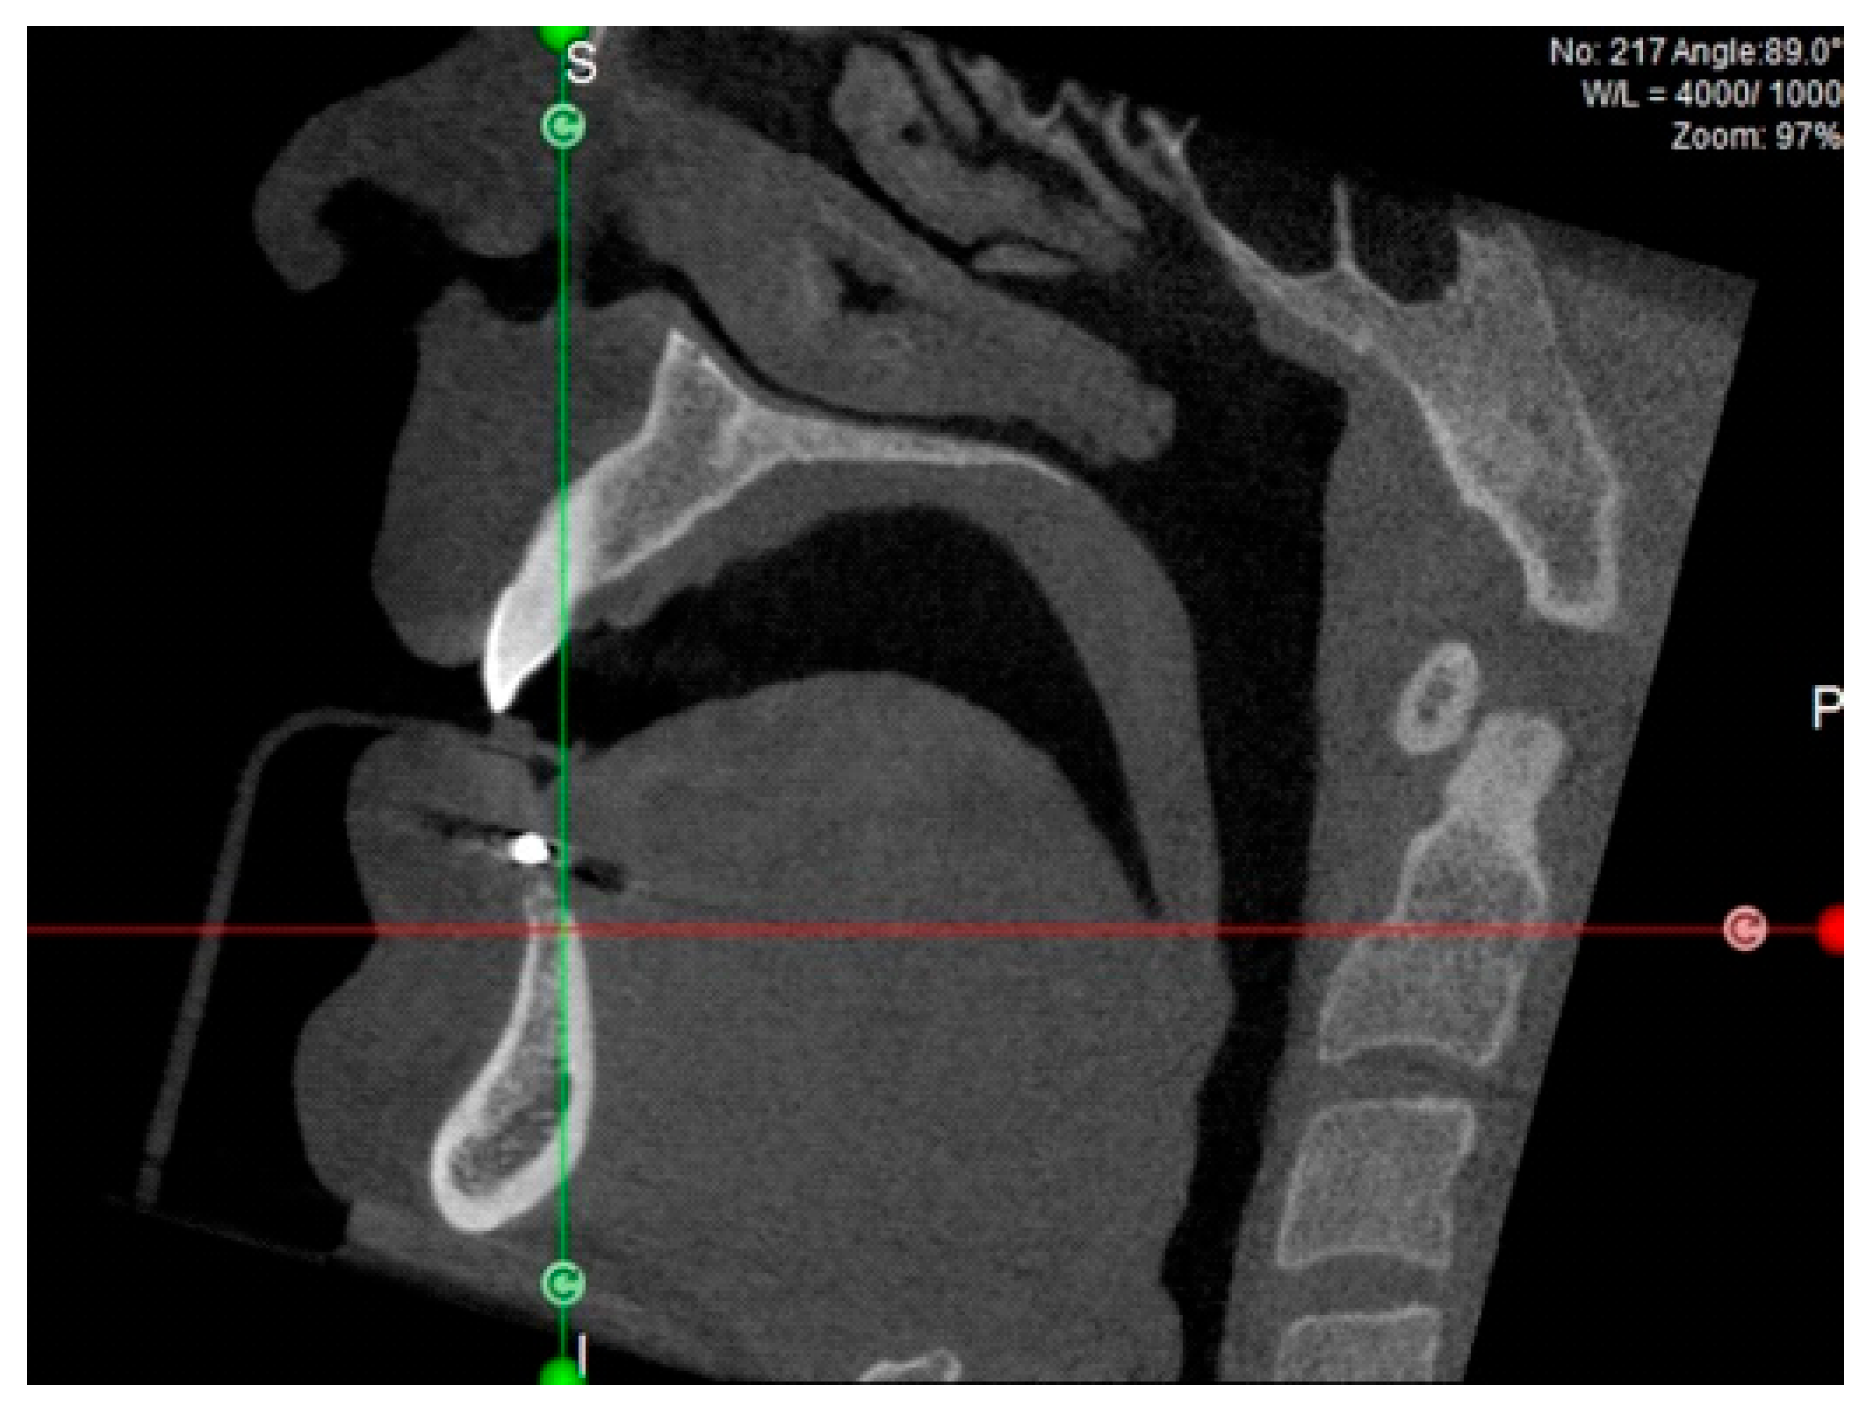

CBCT taken with template | Definitive patient selection Elegibility criteria: fixture position confirmed by CBCT |